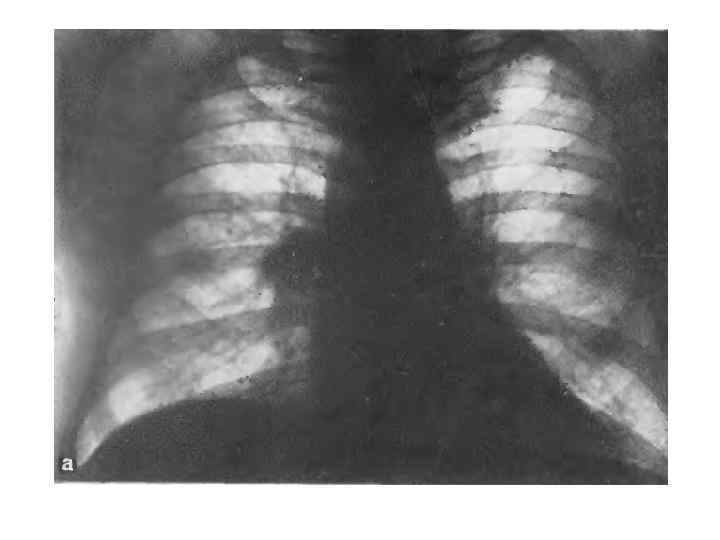

Рентгенологическая семиотика Рентгенологическая картина центрального рака обусловлена: самой опухолью; возникающим нарушением бронхиальной проходимости; осложнениями, развивающимися в связи с прогрессирующим ростом опухоли и метастазами. Преимущественно эндобронхиальный (внутрь) рак Рассматривая рентгенологическую симптоматику и клиническую картину эндобронхиального рака с момента его возникновения, следует выделить определенные фазы его развития (табл. 5). Первая фаза соответствует минимальным размерам опухоли, когда клиническая и рентгенологическая картины не дают оснований для постановки диагноза. В этой фазе отсутствуют клинические симптомы, рентгенологически тень опухоли или ее косвенные признаки не определяются. Дальнейший рост узла приводит к сужению бронха и нарушению вентиляции сегмента, что указывает на существование опухоли, хотя сама по себе она рентгенологически не видна. Наступает вторая фаза развития опухоли, которая проявляется гиповентиляцией сегмента, отражающей стадию нарушения бронхиальной проходимости. Сужение просвета брон хиальной ветви приводит к недостаточному поступлению воздуха в дрени руемый сегмент легкого. Последний на фоне воздушного легкого приоб ретает несколько меньшую прозрачность, сосуды его сближаются, что свя зано как с меньшим поступлением воздуха в этот сегмент, так и с расши ренном кровеносных сосудов. Возникает застойная гиперемия ввиду понижения внутриальвеолярного давления (рис. 227).

Возникает застойная гиперемия ввиду поннжения внутриальвеолярного давления (рис. 227). Развивается сегметарная гиповеитнляция, которая наиболее отчетливо улавливается в фазе максимального вдоха. Поэтому обычным рентгенологическим приемом при просвечивании должно быть детальное изучение воздушности легких в фазе задержанного глубокого вдоха. В этой стадии при резком вдохе можно заметить толчкообразное смещение органов средостения в больную сторону (положительной симптом Гольцкнехта — Якобсона). При сегментарных поражениях этот симптом может быть неясно выражен и его отсутствие не позволяет снять подозрение на нарушение бронхиальной проходимости. Следует провести также пробу кашлевого толчка (по А. Е. Прозорову), который иногда вызывает более выраженное толчкообразное смещение средостения в сторону поражения в связи с меньшим давлением в гиповентилируемом сегменте легкого. В этой I стадии нарушения бронхиальной проходимости большое значение приобретает тщательный анализ легочного рисунка. Некоторое сгущение сосудистого рисунка, связанного с расширением сосудов, небольшое объемное уменьшение пораженного сегмента из за гиповентиляции по сравнению с противоположной стороной должны заставить подумать о нарушении бронхиальной проходимости.